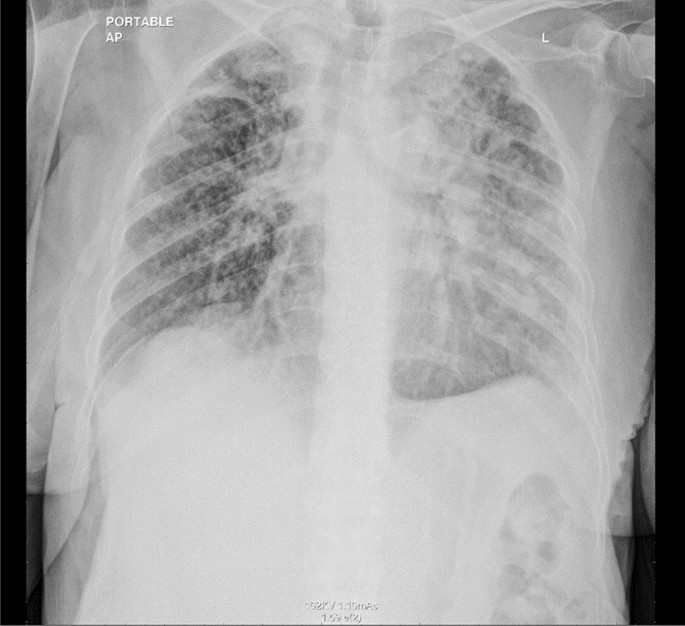

2 weeks later, chest X-ray showed new bilateral reticular, and nodular pulmonary infiltrates (Fig. 7).

Chest X-ray showed new bilateral reticular and nodular pulmonary infiltrates.